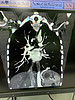

В Центре онкологии и медицинской радиологии продолжается совершенствование оказания медицинской помощи пациентам, в том числе торокального профиля. В декабре в торакальное отделение с кровохарканьем в экстренном порядке поступил 21-летний кировчанин. Пациенту провели компьютерную томографию, по результатам которой у него была диагностирована секвестрация легкого. При данном пороке участок органа не связан с бронхами и кровоснабжается из аномальных артерий.

– Молодого человека доставили к нам бригадой скорой помощи, мы оперативно провели ему исследование. При первом просмотре я увидела, что у пациента нетипичное строение легкого, после более детального изучения стало понятно, что у него секвестрация легкого. Сосуд из чревного ствола, который находится в брюшной полости, проходит через диафрагму в грудную клетку. Из-за этого происходит сдавливание диафрагмального нерва, что в результате вызывает кашлевые рефлексы. На фоне простуды пациент начал сильно кашлять, и мелкая ветвь сосуда лопнула, что вызвало кровохарканье, – рассказала заведующая отделением рентгенодиагностики №2 Центра онкологии и медицинской радиологии Анна Михалина.